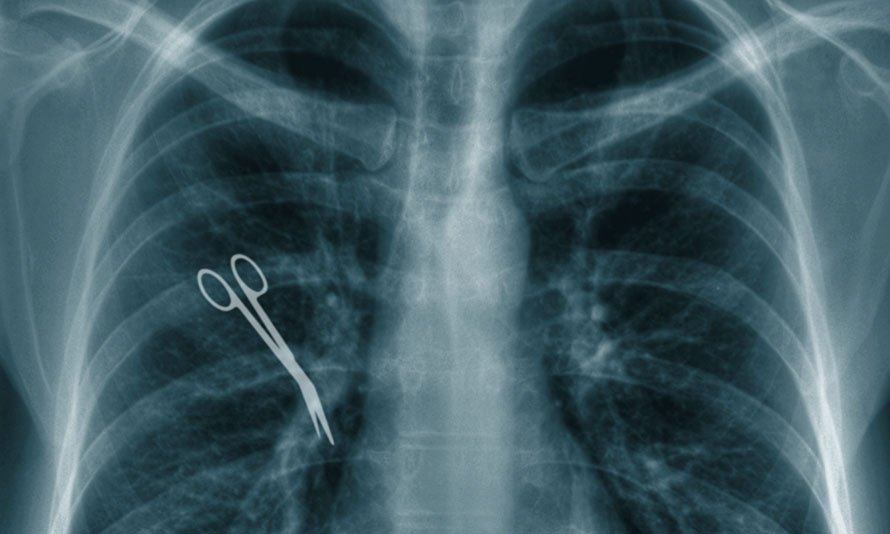

Nerve damage or paralysis can be a devastating outcome of surgical malpractice in New York for patients who trust their healthcare providers to perform procedures with the utmost care. Nerve damage can result from a surgeon’s negligence, such as improper technique, lack of precision, or failure to identify and protect critical nerves during surgery. This type of malpractice can lead to partial or complete paralysis, severely impacting a patient’s quality of life, mobility, and independence.